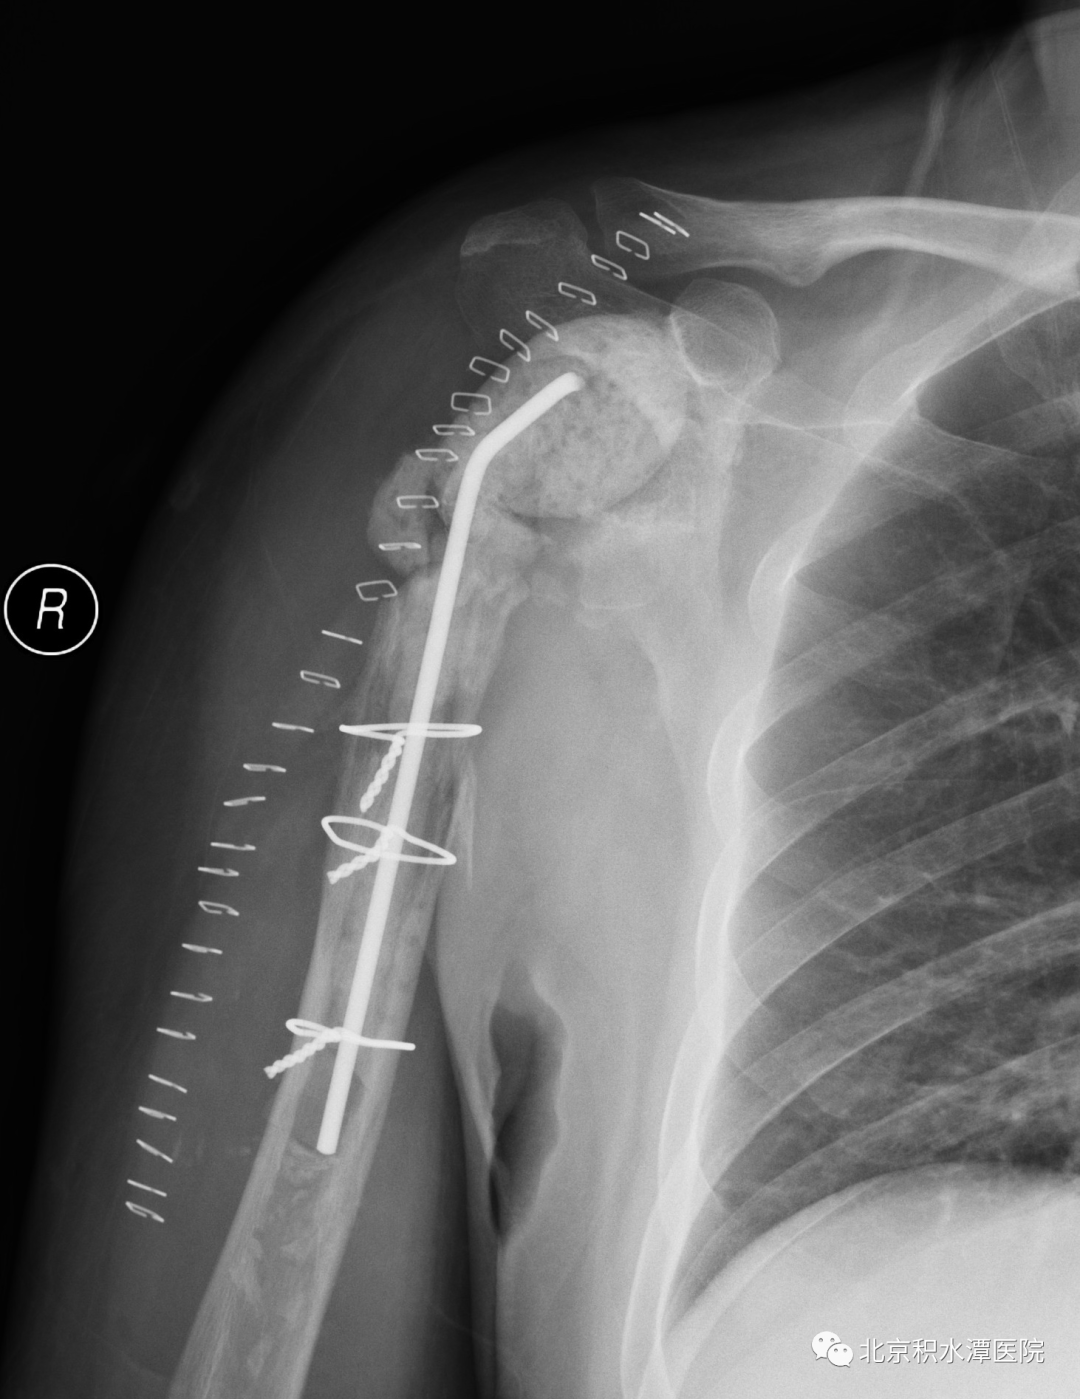

2022年8月18日,患者再次回到北京积水潭医院,蒋协远教授带领黄强主任医师和查晔军副主任医师、公茂琪主任医师等为患者进行了APC反肩置换手术治疗。术中见肩胛盂骨性结构重建良好,取出螺钉,顺利安装肩盂侧反球假体。并反复通过测量和软组织张力判断,确定了异体骨长度,安装肱骨侧假体后,以异体骨板捆扎保护,手术过程顺利,拍片见肩关节假体位置满意。